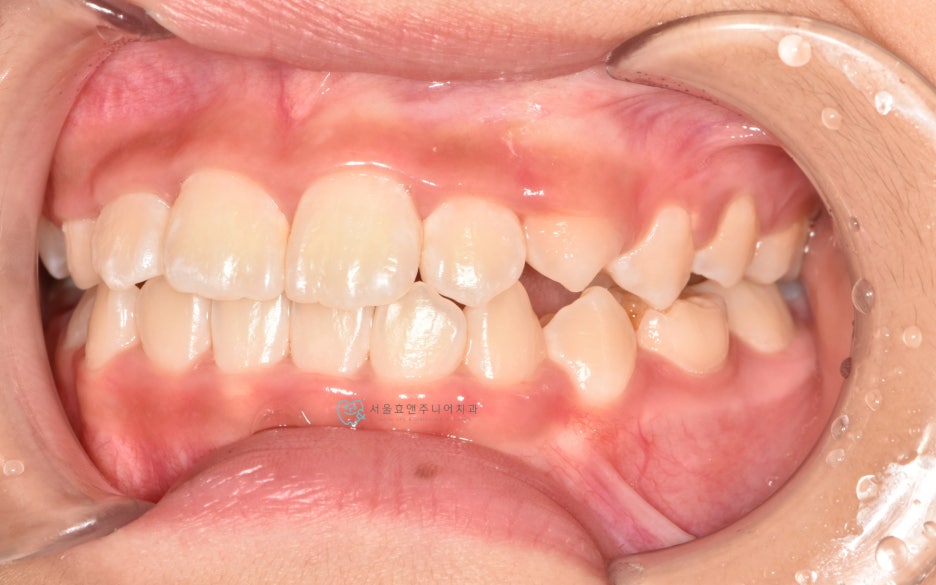

너무 예쁜 10세 11개월의 여자친구인데 반대교합이 있네요.

초진사진입니다. 앞니의 반대교합이 보입니다.